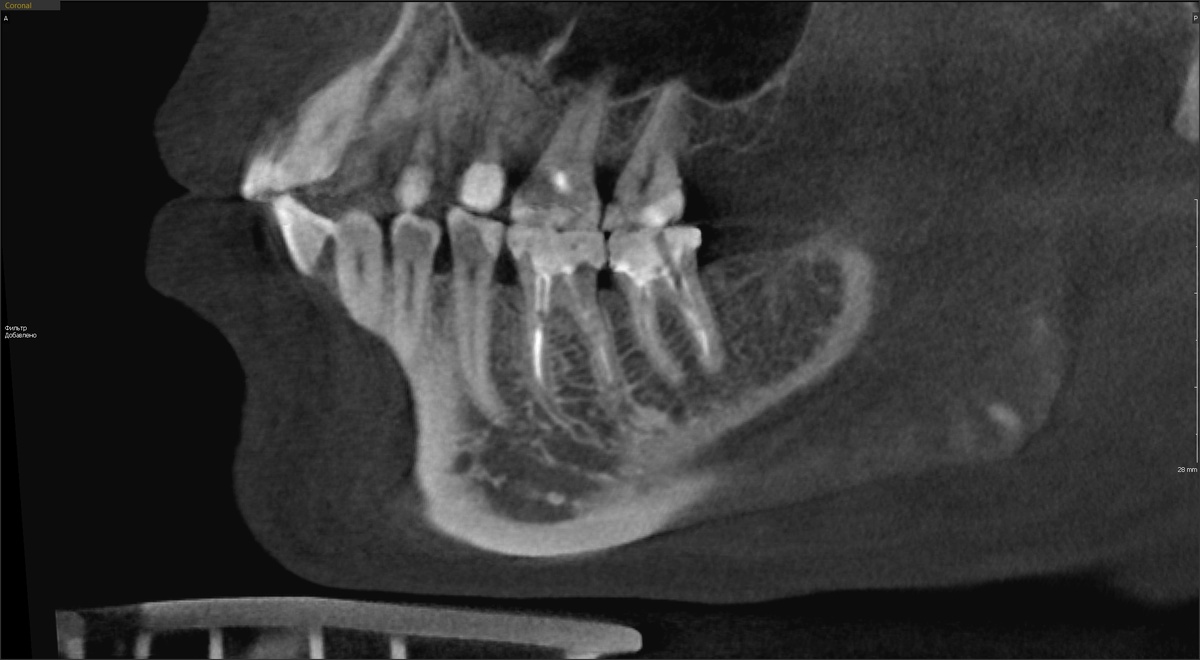

Проверили качество эндодонтии по КЛКТ. Даю один срез, но мы крутили зубы многообразно - со всех сторон узрели всё.

-2

Каналы запломбированы хорошо, периапикальных изменений нет. Казалось бы, работа ожидается простая - установить коронки и всё. Плёвое дело. Смущали только жёлтые штифты.